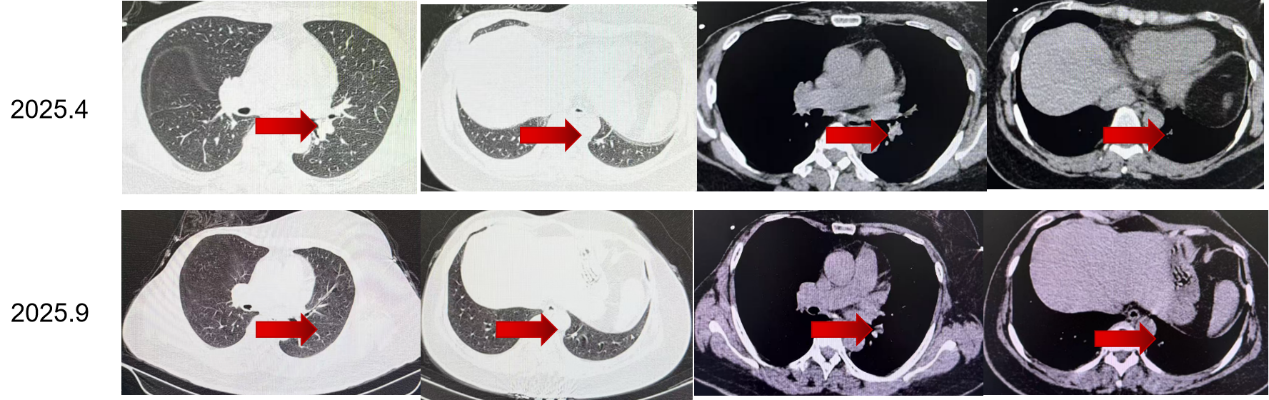

换用达尔西利联合阿那曲唑后,患者后续多次复查均提示病灶进一步缩小,2024年8月、2024年11月、2025年4月及2025年9月疗效评价均为PR。靶病灶总和由55 mm降至20 mm,整体缩小约63.6%,提示调整方案后患者获得了持续且稳定的影像学缓解。

从病程时间轴来看,患者术后至复发的DFS为14年8个月;初始一线治疗阶段获得了早期疾病控制,而在后续调整为达尔西利联合阿那曲唑后,至今持续获益中。对于需要兼顾疗效与治疗连续性的HR+/HER2-晚期乳腺癌患者而言,这一结果提示,在后续治疗策略优化后,患者仍有机会持续从CDK4/6抑制剂联合内分泌治疗路径中获益。

从循证角度看,DAWNA-2研究显示,达尔西利联合来曲唑或阿那曲唑一线治疗可显著延长HR+/HER2-晚期乳腺癌患者的无进展生存[1]。同时,已有公开整理资料显示,DAWNA-2研究中达尔西利因不良反应停药率为4.0%,提示其在长期维持治疗中的安全性管理具有一定现实优势。而在本例中,患者调整为达尔西利联合阿那曲唑后,多次疗效评估均达到PR,且截至2025年9月已获得超过15个月的持续无进展获益,提示在总体治疗路径保持一致的前提下,后续通过更契合患者安全性需求的药物优化,仍有望帮助患者持续维持疾病控制。